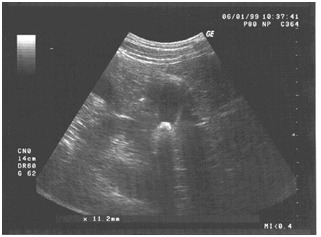

Before the start of the course of laser therapy, the patient complained of impaired well-being, a feeling of heaviness and constant pulling pains in the right hypochondrium, dyspeptic disorders. The patient for a long time used painkillers, spasmolytic and enzyme preparations. The performed ultrasound examination revealed deformation and echo signs of inflammation of the gallbladder wall, presence of calculus in the gallbladder, expansion of the hepatic bile ducts. The immobility of the concernment when the patient's body was changed was evidence of its adhesion to the wall of the gallbladder. The maximum size of the calculus in the initial ultrasound examination (before the laser therapy course) was 18.3mm (Figure 1). The test with food load (2 raw eggs, eaten on an empty stomach) revealed a significant decrease in the contractility of the gallbladder walls. In the experiment we used the infrared laser therapeutic apparatus "Binom" (Russia). As laser exposure methods, the following methods were used: the method of polygonal sequential transcutaneous laser action on the vascular plexus1–3 and the method of polygonal transcutaneous laser action on the anatomical projections of the liver (right lobe) and the gallbladder (Figure 2). Particular mention should be made of the absolute painlessness and ease of laser procedures.

Figure 1 Initial (before the start of laser therapy) data of ultrasound examination of the gallbladder patient.

Data from the final ultrasound (at the end of the 6-week course of treatment) revealed an actual absence of echoes of inflammation of the gallbladder wall, mobility of the calculus and a reduction in its maximum size to 11.2mm (Figure 3). Ultrasound examination after a nutritional load indicated some hyperkineticity of the gallbladder wall (a reduction in the volume of the gall bladder 77% of the original). The course of treatment of the patient T. F-ko was interrupted in connection with her departure for a long period abroad. During the following years, experimental work was continued to investigate the possibility of conservative treatment of cholelithiasis complicated by chronic cholecystitis, involving volunteer patients. During this period, 7 people (3 men and 4 women) aged 35 to 54years old participated in the experiments, with different physique, severity and length of illness.